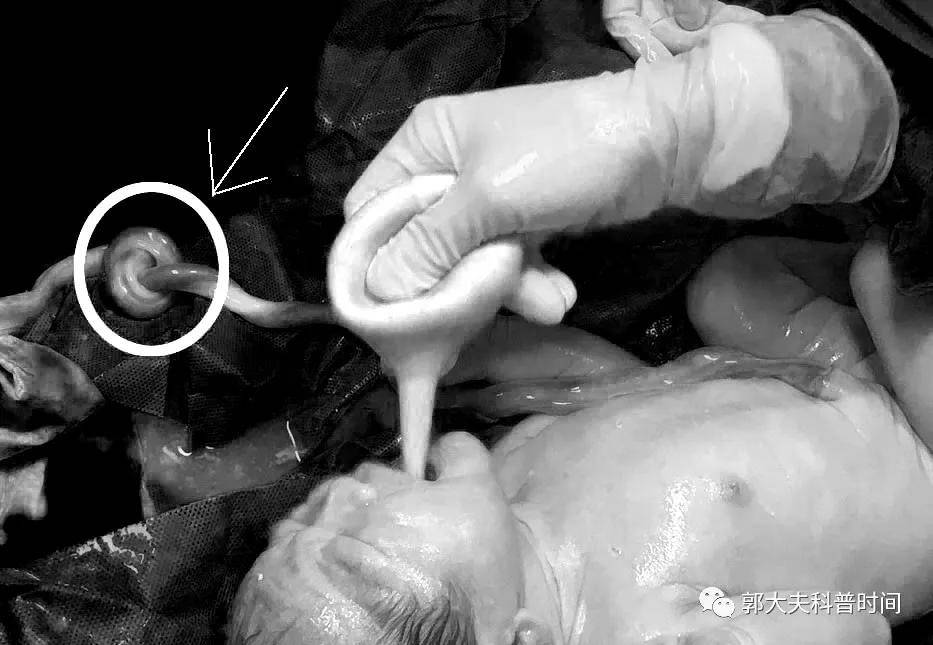

最后探究该胎儿发生缺氧的原因 , 可能和脐带扭转有关 。 大多数情况下 , 脐带扭转并不会导致缺氧 , 但是扭转的脐带如果受到牵拉 , 就会出现管腔狭窄 , 从而导致缺氧 。 不过C是幸运的 ,宝宝缺氧整个过程都是发生在医生眼皮底下 , 剖宫产的时候发现羊水居然还是非常清澈的 , 这就意味着孩子并没有因为短暂的缺氧造成损害 。

下面这个宝宝也是最近两天分娩的 , 幸好脐带长度足够 , 否则就是自己了结自己的命运 。